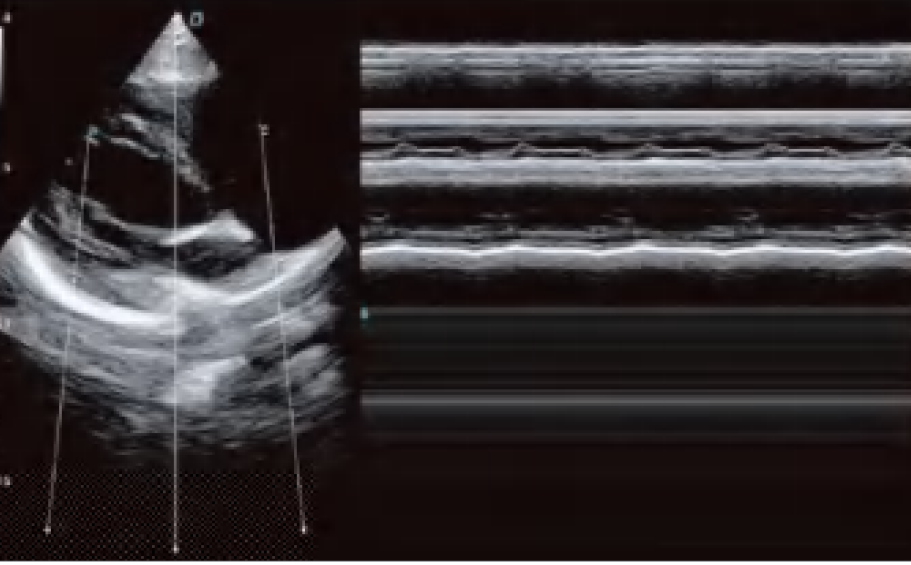

El DW-L50 Exp, impulsado por la avanzada plataforma de ultrasonido ST-U, ofrece imágenes ultra claras en todo momento. Con una movilidad y adaptabilidad sobresalientes, funciona de manera fiable en diversos entornos clínicos complejos. Su introducción permite que más instituciones médicas accedan a tecnología de ultrasonido rentable y de alto rendimiento.